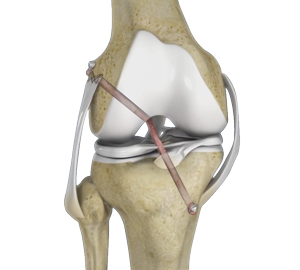

Multiligament Reconstruction of the Knee

Multiligament Knee Reconstruction Surgeon in Palm Beach Gardens & Wellington People who have high-energy knee injuries where multiple knee ligaments are torn …